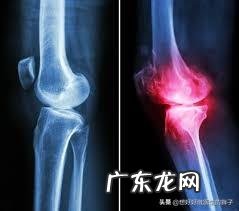

当我们的关节软骨在体重增加、长时间的过度使用、不正确的运动、外伤以及寒凉等因素的刺激下 。关节内的软骨就会发生磨损,由于关节内的软骨会有一定的厚度,在磨损的早期只会发生类似于天鹅绒样的改变,患者并不会有特殊的症状,只有在特殊的查体或者是特殊的体位,与动作的时候,会诱发轻度的疼痛 。比如很多老年患者会在上下楼梯和蹲起的时候感觉到膝关节前方的疼痛,走平路反而没有症状,这就是骨关节炎早期的一种特殊表现 。

但是如果磨损进一步的加重,那么就会出现软骨的剥脱碎裂,患者的疼痛可能就会越来越严重,在此阶段的患者通常会走平路的时候,也会有明显的疼痛,做x线检查,基本会发现关节间隙已经开始出现了狭窄,而且会有骨赘也就是骨刺的形成 。

当病程进行到了晚期,患者关节间隙会越来越严重,关节也会随之出现明显的变形,有的老年人会出现明显的o型腿,或者是x型腿的改变,基本都是源自于关节内软骨的磨损,导致的关节畸形 。而患者呢,也会出现明显的关节疼痛,严重影响患者的生活质量,有一些患者会出现明显的夜间痛以及休息痛 。